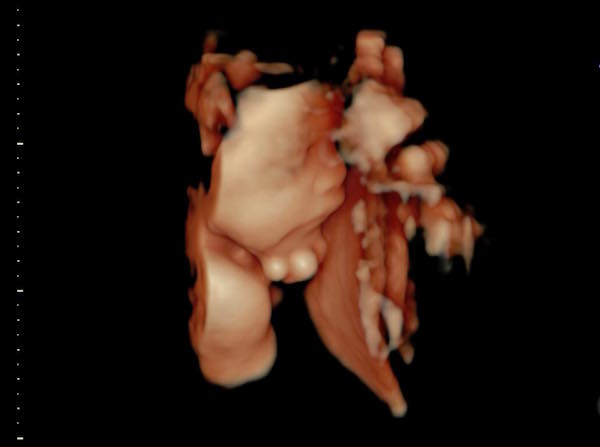

▼最近她有貼出女兒超音波照,顯示Tammy竟在裡面比出「YA」的手勢,崩潰失笑說:「媽咪每天嗑一堆藥辛苦安胎~妳在裡面倒是挺開薰的嘛!還有空比YA勒…算妳狠!」也附註Tammy已經有1300多公克,「給我乖乖待著,時間到了才准出來嘿!」

▼從照片中也可以看到,Tammy照片漸漸清晰,長得與哥哥Willson十分神似,讓嚴立婷也很期待妹妹能出生,「覺得以後兄妹會長很像,你們說如果Tammy像Willson是不是挺不賴的?」Tammy小腿也相當修長,底下網友大贊遺傳父母優秀基因,以後一定是「小美女」。